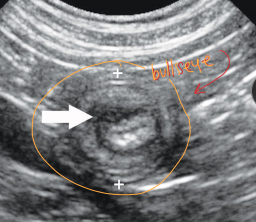

Dt: Normal Rads(chest/abd.), Contrast GI studies(thickening), Fluoroscopy(funct. dysphagia), US(mass/hernia)

Dt: PE, Palpation, survey Rads #1 ± contrast, US(more sensitive)

dilated loops, stacking, gas pattern

Comma-shaped gas bubbles

Dt: Palpation, rads, US